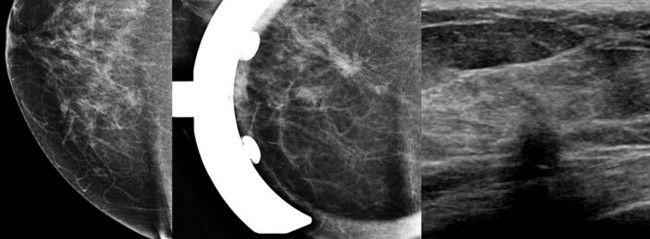

FIGURE 11-3 Shrinking Breast.

A 52-year-old woman noted thickening in her left breast. On clinical examination, the breasts are symmetric in size but the texture of the left breast is diffusely thickened. On mammography, the left breast appears to be smaller than the right. Biopsy showed ILC. Did you also notice the one-view asymmetry in the right medial breast? US of this area shows a small hypoechoic mass. Biopsy of the right breast showed IDC.